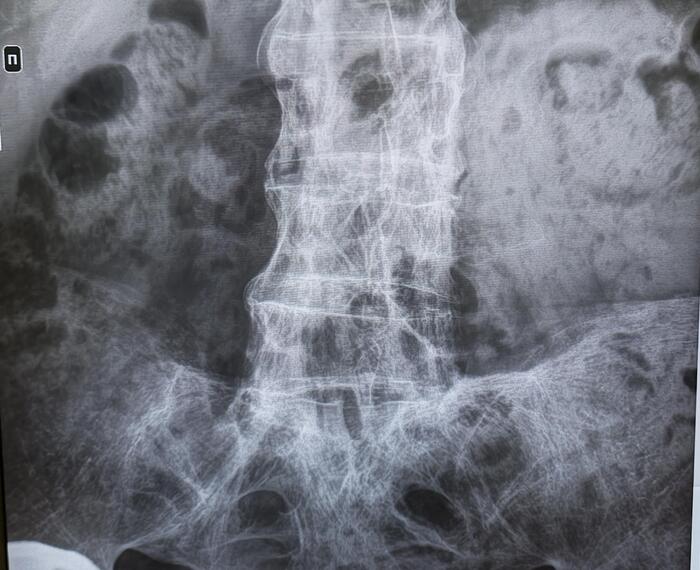

Рентгенография - в начальной стадии при подагре почти не дает информации; при длительном течении, когда кристаллы накапливаются внутри кости, их видно как четкие округлые образования - “пробойник ”.

При пирофосфатной артропатии иногда можно увидеть кальцификацию суставного хряща.